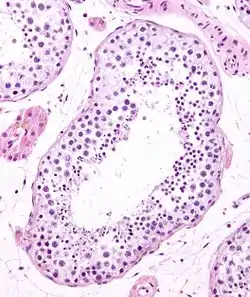

Seminiferous tubule in cross-section (large tubular structure – center of image) with sperm (black, tiny, ovoid bodies furthest from the outer edge of the tubular structure). H&E stain.

Seminiferous tubules are located within the testicles, and are the specific location of meiosis, and the subsequent creation of male gametes, namely spermatozoa.

The epithelium of the tubule consists of a type of sustentacular cells known as Sertoli cells, which are tall, columnar type cells that line the tubule.

In between the Sertoli cells are spermatogenic cells, which differentiate through meiosis to sperm cells. Sertoli cells function to nourish the developing sperm cells. They secrete androgen-binding protein, a binding protein which increases the concentration of testosterone.